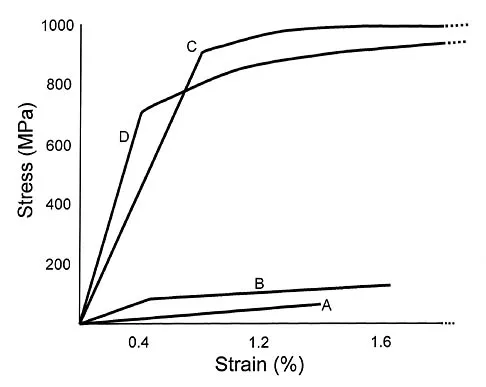

Which of the following best describes the mechanical response of the inferior glenohumeral ligament to repetitive subfailure strains?